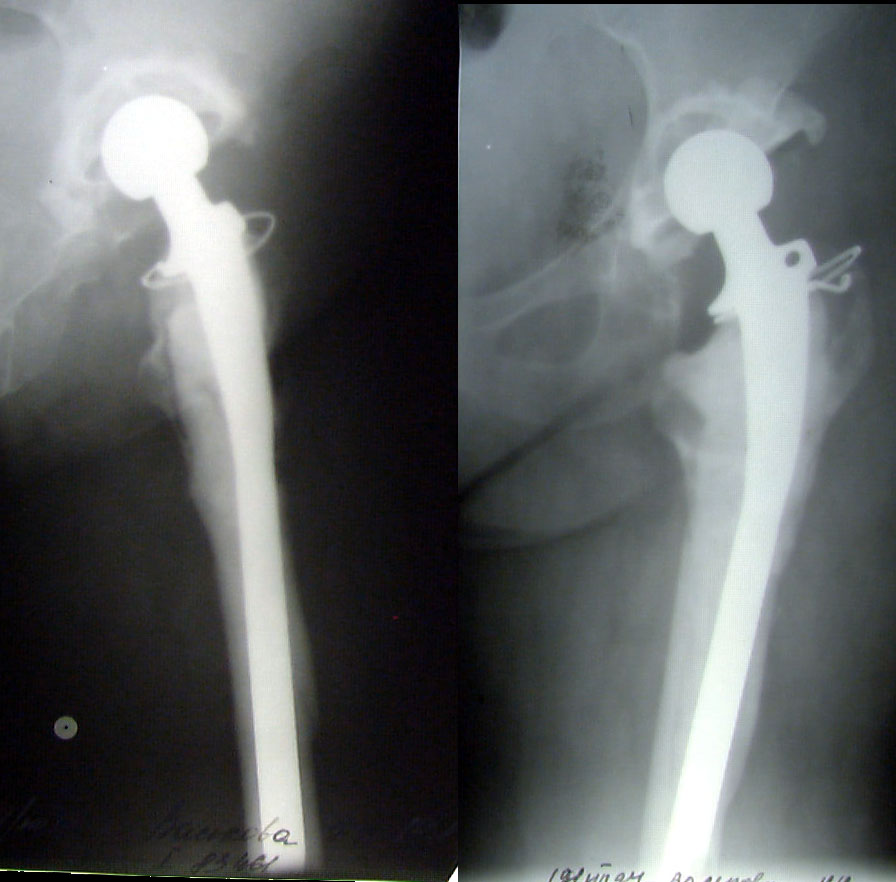

ÊÎÑÒÍÎÏËÀÑÒÈ×ÅÑÊÎÅ ÓÊÐÅÏËÅÍÈÅ ÂÅÐÒËÓÆÍÎÉ ÂÏÀÄÈÍÛ ÏÐÈ ÒÎÒÀËÜÍÎÌ ÝÍÄÎÏÐÎÒÅÇÈÐÎÂÀÍÈÈ ÏÎ ÏÎÂÎÄÓ ÄÈÑÏËÀÑÒÈ×ÅÑÊÎÃÎ ÊÎÊÑÀÐÒÐÎÇÀ ÊÎÑÒÍÎÏËÀÑÒÈ×ÅÑÊÎÅ ÓÊÐÅÏËÅÍÈÅ ÂÅÐÒËÓÆÍÎÉ ÂÏÀÄÈÍÛ ÏÐÈ ÒÎÒÀËÜÍÎÌ ÝÍÄÎÏÐÎÒÅÇÈÐÎÂÀÍÈÈ ÏÎ ÏÎÂÎÄÓ ÄÈÑÏËÀÑÒÈ×ÅÑÊÎÃÎ ÊÎÊÑÀÐÒÐÎÇÀ Âîëîøèí Â.Ï., Ìàðòûíåíêî Ä.Â., ÌÎÍÈÊÈ, Ìîñêâà, Ðîññèÿ

Êàðòèíêà Êàðòèíêà

ÝÍÄÎÏÐÎÒÅÇÈÐÎÂÀÍÈÅ ÏÐÈ Ò߯¨ËÛÕ ÔÎÐÌÀÕ ÏÀÒÎËÎÃÈÈ  ÒÀÇÎÁÅÄÐÅÍÍÎÃÎ ÑÓÑÒÀÂÀ ÝÍÄÎÏÐÎÒÅÇÈÐÎÂÀÍÈÅ ÏÐÈ Ò߯¨ËÛÕ ÔÎÐÌÀÕ ÏÀÒÎËÎÃÈÈ ÒÀÇÎÁÅÄÐÅÍÍÎÃÎ ÑÓÑÒÀÂÀ Õ.Ç.Ãàôàðîâ, È.À.Âàëååâ, À.Ð.Ñàãäåàâ, À.Ø.Ôàéçååâ, ÍÈÖÒ ÂÒÎ, Êàçàíü, Ðîññèÿ

ÝÍÄÎÏÐÎÒÅÇÈÐÎÂÀÍÈÅ ÒÀÇÎÁÅÄÐÅÍÍÎÃÎ ÑÓÑÒÀÂÀ ÝÍÄÎÏÐÎÒÅÇÎÌ SLPS ÝÍÄÎÏÐÎÒÅÇÈÐÎÂÀÍÈÅ ÒÀÇÎÁÅÄÐÅÍÍÎÃÎ ÑÓÑÒÀÂÀ ÝÍÄÎÏÐÎÒÅÇÎÌ SLPS Ðóöêèé À.Â., Ìèíñê, Áåëîðóññèÿ